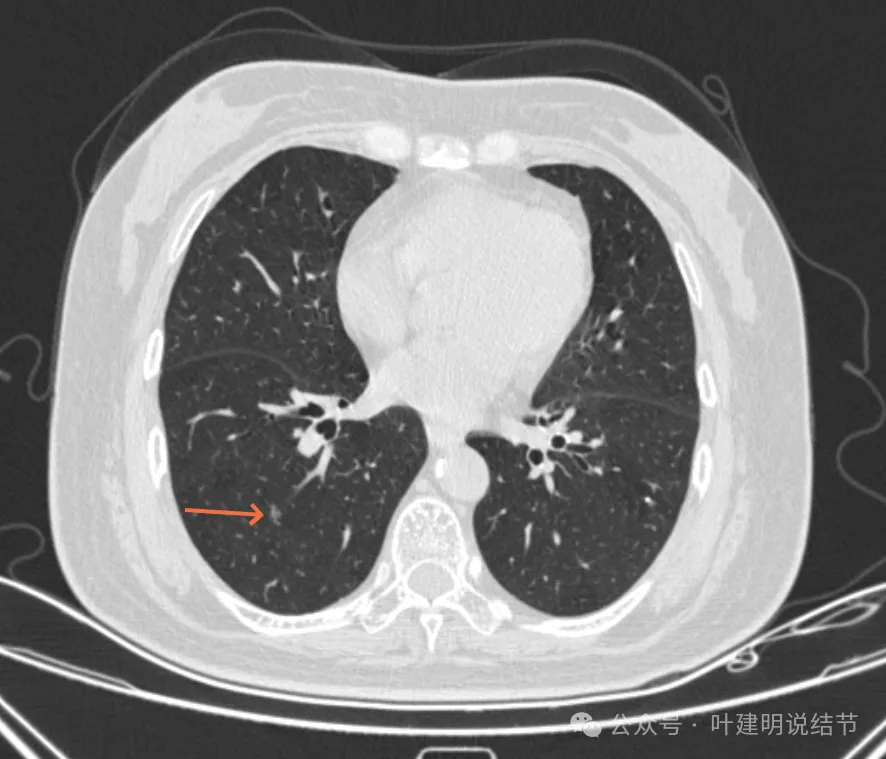

病灶10:右侧胸膜下淡磨玻璃结节,轮廓较清。

病灶32:上叶尖后段胸膜下此灶密度较高,有小血管进入,但病灶本身还小,考虑原位癌可能性稍大。